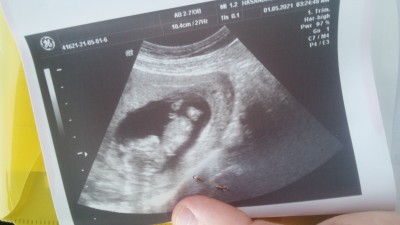

Merhaba az önce doktora gittim özele bazen erken söylüyorlar bi umut dedim ama henüz çok erken yorum yapmak istemiyorum dedi sizce cinsiyeti ne olabilir bacak arası boş gibi idi bana kız gibi geldi tekme atıyordu gördüm ilk kez annelik duygusunu hissettim sağlıkla kucağıma alırım inş. Bekleyen herkes sağlıkla kavussun ins

12+1

Bana da kız gibi geldi :)